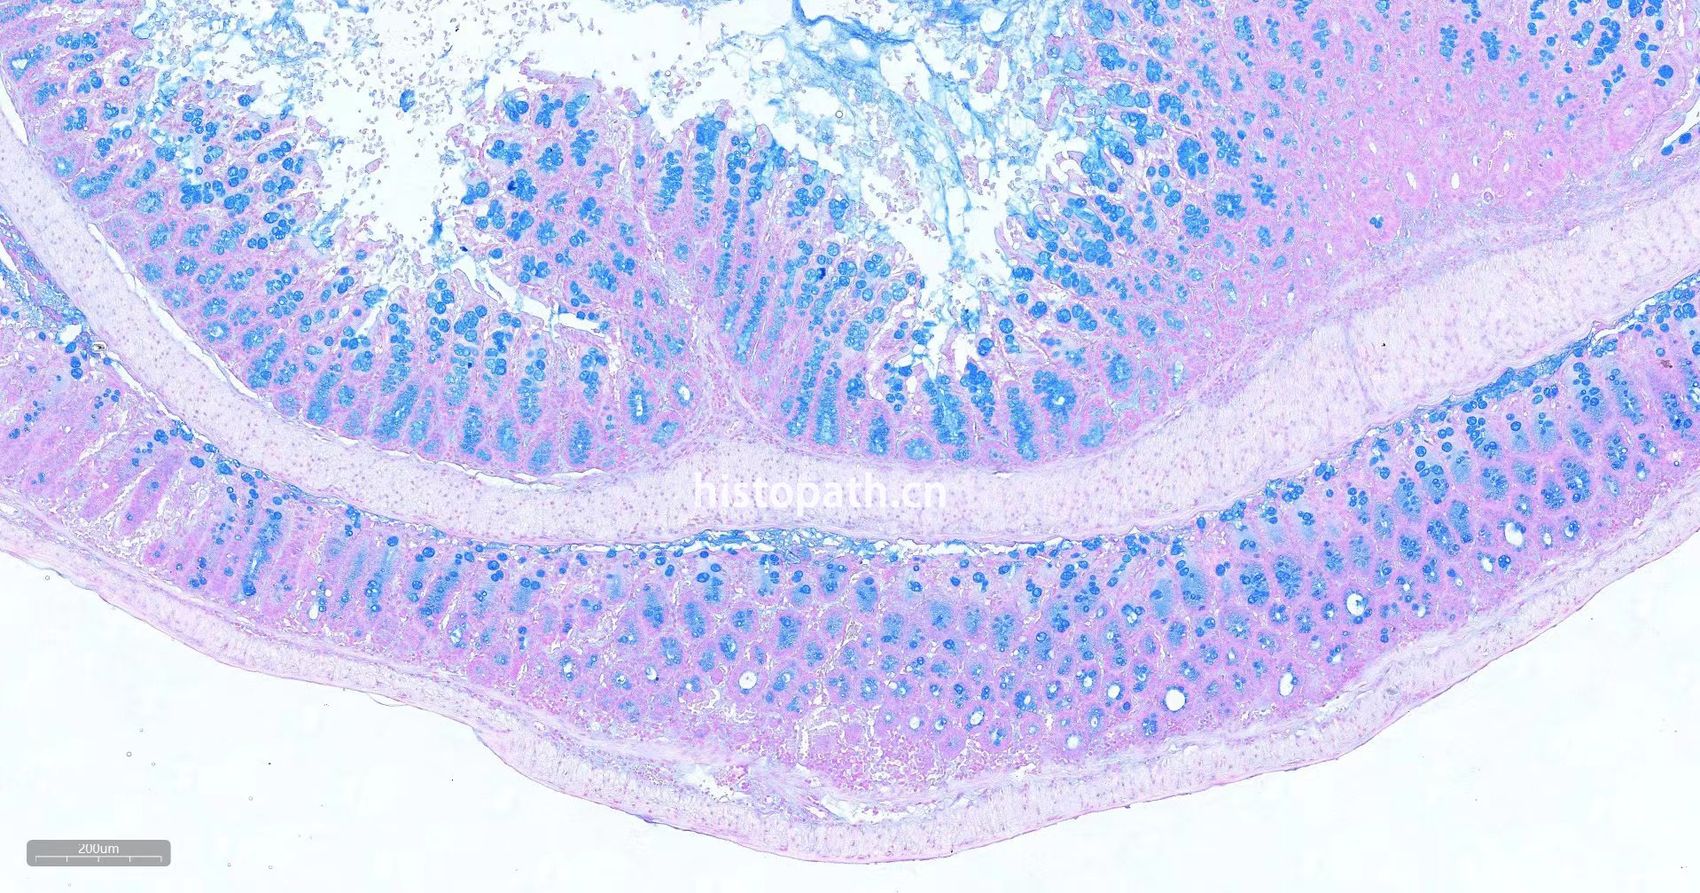

肠卷阿利新蓝染色

阿利新蓝.jpg阿利新蓝.jpg阿利新蓝11.jpg